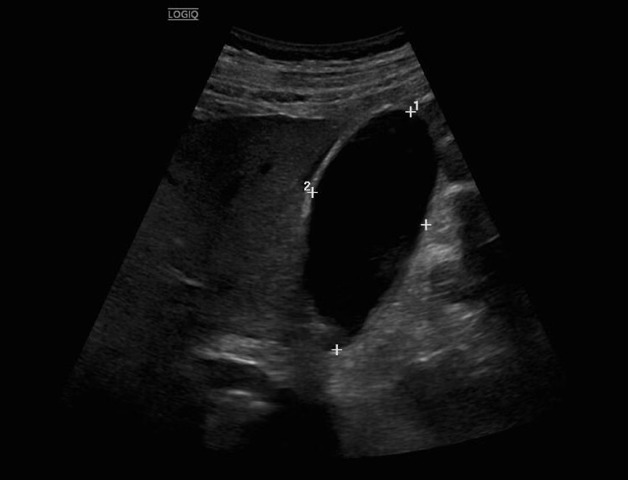

La ecografía abdominal urgente muestra engrosamiento parietal del colon descendente-sigma-recto, aumento de ecogenicidad de la grasa pericólica e hiperemia, compatibles con colitis izquierda.

La ecografía abdominal urgente permitió identificar precozmente un proceso inflamatorio colónico, orientar el diagnóstico diferencial y priorizar la realización rápida de tomografía, detectando una complicación abscesificada. Este caso destaca el valor de la ecografía en Medicina de Familia como herramienta accesible, resolutiva y clave para mejorar la seguridad, optimizar derivaciones y reducir tiempos asistenciales.